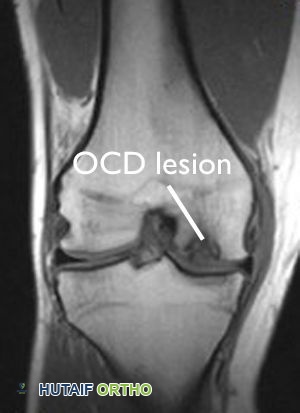

- التصوير بالرنين المغناطيسي (MRI): يُعد التصوير بالرنين المغناطيسي أداة تشخيصية قوية جداً. يمكنه إظهار مدى الضرر الذي لحق بالغضروف، وتقييم حالة العظم الكامن، وتحديد ما إذا كانت الآفة مستقرة أو غير مستقرة، وما إذا كانت هناك سوائل متجمعة تحتها، مما يشير إلى انفصال محتمل.

يُظهر هذا الفحص بالرنين المغناطيسي آفة التهاب العظم والغضروف السالخ في عظم فخذ مريض يبلغ من العمر 18 عاماً.